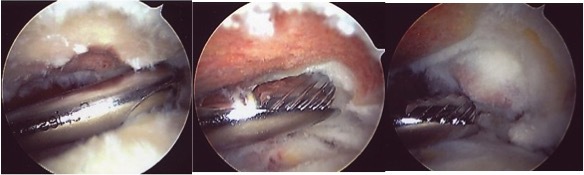

The procedure is performed under a combination of general and regional anaesthesia. An arthroscope is inserted into the joint after distending it with saline. The inside of the joint and subacromial bursa are examined. The undersurface of the acromion is exposed with the aid of a radiofrequency probe and a small amount of bone is removed with the aid of an arthroscopic shaver (motorised burr).